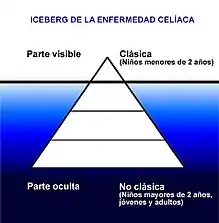

Se ha descrito que la sintomatología de la celiaquía podría compararse gráficamente como un “iceberg”, en el que la parte visible y clínicamente manifiesta corresponde a las denominadas “formas clásicas”, que predominan en la temprana infancia, mientras que las “formas no clásicas” u oligosintomáticas son las que aparecen de forma predominante en los niños mayores de 2 años, adolescentes y adultos en general, constituyendo su parte oculta muy importante, ya que representan más del 75 % de los casos.[27][41]

Los síntomas que se creían siempre presentes en personas celiacas, que incluyen malabsorción grave con diarrea crónica, signos de malnutrición y retraso del crecimiento (presentación clásica), son actualmente excepcionales, especialmente en niños mayores de dos años y adultos. La mayoría de las personas de todas las edades presenta molestias digestivas leves o intermitentes y/o síntomas no digestivos (presentación no clásica).[39] Incluso una gran parte de enfermos celíacos son aparentemente asintomáticos a nivel digestivo,[19] [39] [40] [41] normalmente debido a que se han acostumbrado a vivir con un estado de mala salud crónica como si fuera normal[42][43] y al efecto opioide del gluten, que enmascara el daño intestinal.[44] Los síntomas que pueden aparecer son muy variados, no existe un patrón único definido, ni una clínica común para todos los pacientes, puesto que las presentaciones de la enfermedad son múltiples y muy diferentes. Puede cursar con diarrea o estreñimiento, con clínica digestiva florida o sin ningún síntoma digestivo, con pérdida de peso u obesidad, con retraso del crecimiento o crecimiento normal, con o sin abdomen abultado, con o sin otras enfermedades autoinmunes asociadas, etc.[39] Entre los signos y síntomas no digestivos, con frecuencia puede aparecer uno o más de los siguientes, que pueden fluctuar y variar con la edad: cansancio aumentado, dolores de cabeza, depresión, ansiedad, trastornos neurológicos, dolor de huesos o articulaciones, hormigueos o entumecimientos en manos o pies, huesos débiles y frágiles, problemas en la boca (como aftas, boca seca, alteraciones en el esmalte dental, lengua roja, lisa y brillante), dermatitis, procesos alérgicos, ferropenia o anemia, trastornos menstruales, infertilidad o abortos espontáneos, convulsiones, entre otros.[45][46] De hecho, a la celiaquía se la conoce como "la gran imitadora" o "la enfermedad de las múltiples caras".[47] [48] [49]

Los casos de presentación clásica de la enfermedad, que incluyen manifestaciones de un síndrome de malabsorción grave con esteatorrea y signos de malnutrición, son actualmente excepcionales, especialmente en niños mayores de 2 años y adultos. Incluso una parte de enfermos celíacos son completamente asintomáticos a nivel digestivo por períodos de tiempo prolongados.[19][41][39]

- Las formas de presentación de la enfermedad celíaca más frecuentes son las denominadas "no clásicas", que predominan en los adultos, pero que también aparecen en niños por encima de los 2 años y en jóvenes a cualquier edad.

- Las formas clásicas únicamente aparecen en niños menores de 2 años.